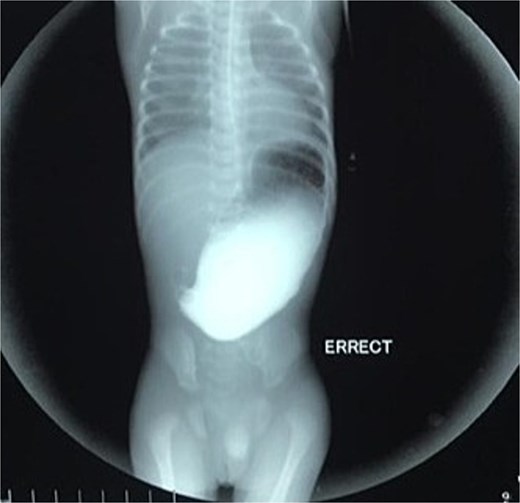

On the ninth day of life, the infant underwent exploratory laparotomy, which confirmed the diagnosis of Type I PA. A markedly dilated stomach with collapsed distal bowel was observed (Fig. 3). Pyloroplasty with transanastomotic nasoduodenal tube placement was performed (Figs 4 and 5). The nasoduodenal tube served as an alternative to parenteral nutrition, which was unavailable in our setting.